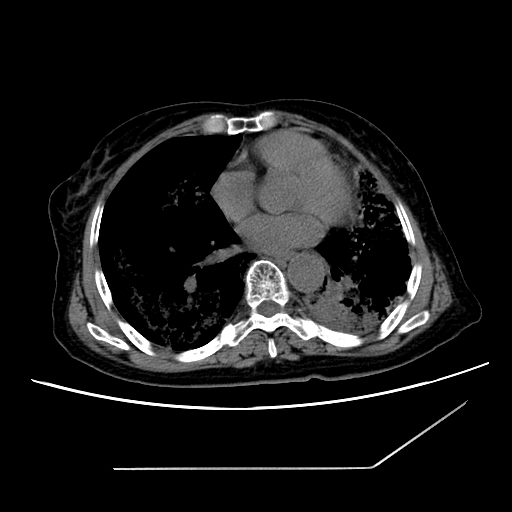

标题: CT25393:病人45岁,咳嗽,吐黄痰带血丝,发热,胸闷月余 [打印本页]

标题: CT25393:病人45岁,咳嗽,吐黄痰带血丝,发热,胸闷月余

1、左肺中央型肺癌并双肺弥漫性转移   2、双肺部感染    3、肺大泡     4、左侧胸腔积液

双侧肺弥漫性病变,可见“空泡征”及“蜂窝征”,考虑肺泡癌可能性大,左侧胸腔积液,考虑胸膜受累可能!

1)不排除肺泡癌可能。2)左侧胸腔积液。